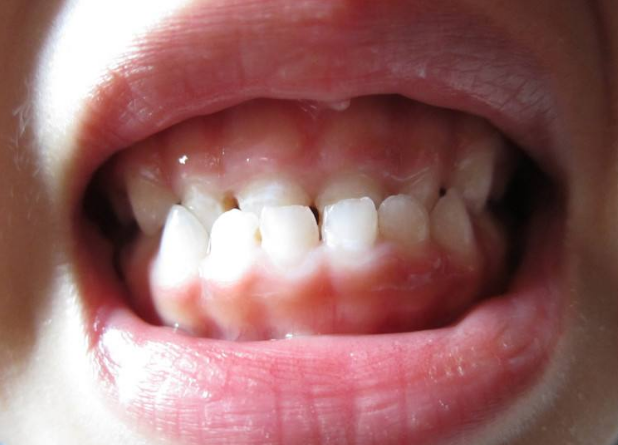

地包天,醫學上稱為反頜,是一種常見的牙齒排列問題。它的特點是下前牙咬合在上前牙的外面,使得下唇明顯前突,形成不正常的面部輪廓。這不僅影響了個人的外貌美觀,還可能引發一系列口腔健康問題。因此,了解地包天的原因、影響以及解決方法至關重要。

地包天不僅影響個人形象,還可能對口腔健康產生負面影響。由于牙齒排列不正常,容易導致食物殘渣堆積,增加齲齒和牙周病的風險。此外,地包天還可能影響咀嚼功能,導致消化不良等問題。因此,對于地包天的治療不容忽視。

珠海六和口腔介紹解決地包天的方法主要包括正畸治療和手術治療。正畸治療通過佩戴牙套等方式,調整牙齒的排列,使其恢復正常。這種方法適用于輕度和中度地包天的患者,療程相對較短,效果也較好。然而,對于嚴重的地包天患者,可能需要采用手術治療。手術方法包括截骨術和正畸聯合手術等,通過調整頜骨的位置和形態,從根本上解決地包天問題。